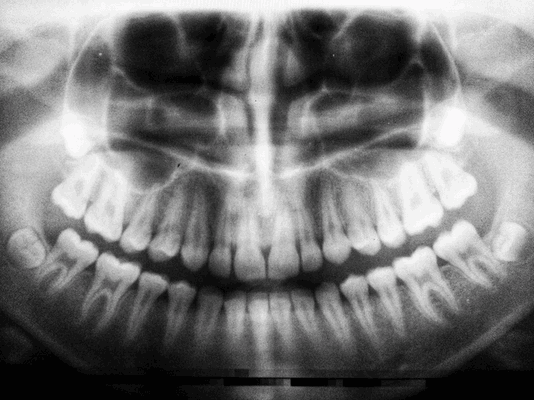

При подготовке к операции большое значение имеет рентген-диагностика, в ходе которой пациент получает панорамный снимок и проходит КТ челюстной кости. На основе результатов этих обследований составляется подробный план санации ротовой полости, подбираются импланты, выбирается метод имплантации.

Из снимков можно выяснить:

- объем, текущее состояние и структуру костной ткани;

- особенности размещения корней, нервов, а также гайморовых пазух;

- имеющиеся патологии в челюстной системе пациента;

- зоны атрофированной костной ткани;

- расположение очагов периодонтита.

Проводится с целью выявить состояние костной ткани и зубных корней, исключить противопоказания. Если вы лечите один зуб, будет достаточно прицельного снимка (рентген). Если врачу необходимо увидеть картину целиком, нужен обзорный снимок (ортопантомограмма). Перед имплантацией вас направят на компьютерную томографию.

Панорамный снимок, КТ. Позволяют увидеть состояние челюстной системы, костной ткани, нервов, носовых пазух. На основании этого врач расписывает план лечения.

Для определения состояния костной ткани проводится пальпация альвеолярных отростков и назначается рентгенографическое обследование (панорамный снимок, ОПТГ). Это позволяет оценить высоту кости и расположение зубов, однако у ОПТГ есть искажения размеров до 20%. Поэтому дополнительно могут назначить компьютерную томографию (КТ) для получения трехмерного изображения строения челюсти.

Чтобы провести диагностику состояния челюсти, врач делает панорамный снимок (ортопантомограмму). На рентгеновском снимке ОПТГ можно увидеть расположение корней зубов, наличие гранулемы, кисты, проседание кости (уровень резорбции), высоту костной ткани. Перед установкой протеза это не менее важные показатели, как и диагностика кариеса, так как по состоянию кости можно определить, какой вид протеза можно установить. Наличие атрофии кости является противопоказанием к установке некоторых видов протезов.